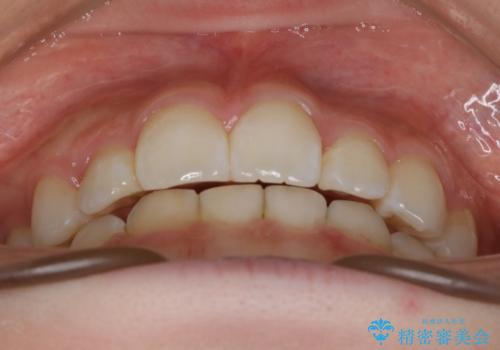

- 歯のガタつきを主訴にご来院されました。

ガタつきがあるだけでなく、元々永久歯が欠損している「先天欠如」で歯の本数が少なく噛み合わせ等も治療する必要がありました。

かなり特殊な状況からの矯正治療になるため抜歯する本数や位置、並んだあとのスペースのコントロールを慎重に計画し、マウスピース装置のインビザラインで治療を開始しました。